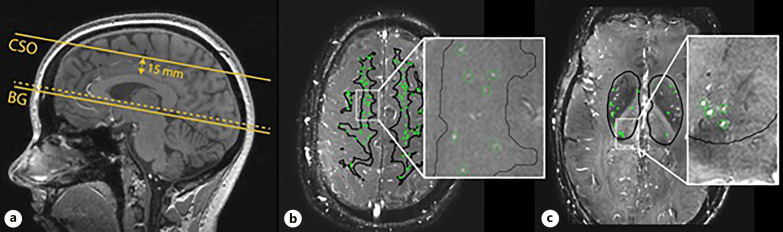

Methods: We measured perforating artery flow with 2D phase-contrast 7 Tesla MRI at the level of the centrum semiovale (CSO) and the basal ganglia (BG) in seventy participants from the Heart Brain Connection study with carotid occlusive disease (COD), vascular cognitive impairment (VCI), or no actual cerebrovascular disease. Vascular risk factors included hypertension, diabetes, hyperlipidemia, and smoking.